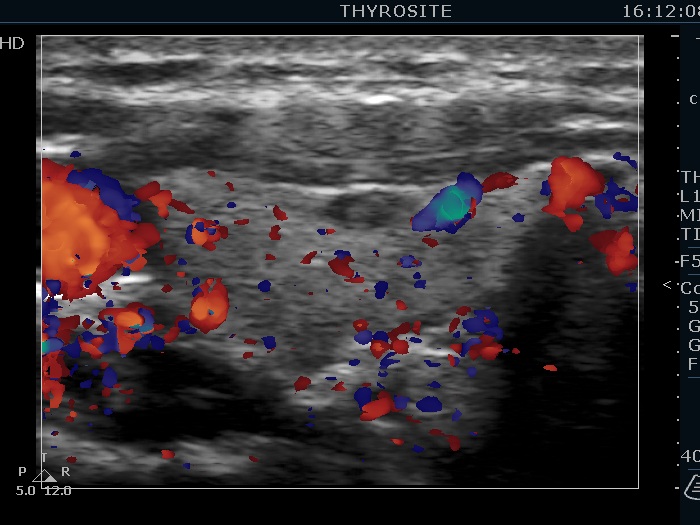

Ultrasonography. The thyroid was echonormal. There were several hypoechoic nodules in the left lobe. The middle one had back wall cystic figures. There were 3 or four discrete, deeply hypoechoic lesions above and lateral to the left lobe in the neck. One of them presented with a hilum-like figure while the others lacked hilum.

The lymph nodes had a non-typical presentation. They lacked a regular hilum.